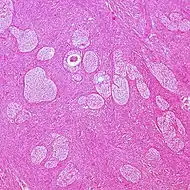

| Surface epithelial-stromal tumor | Serous tumor | 25% | 18.5% | Benign serous tumors of the right ovarian cyst are thinwalled unilocular cysts that are lined by ciliated pseudostratified cuboidal or columnar epithelium.[6] | ![]() |